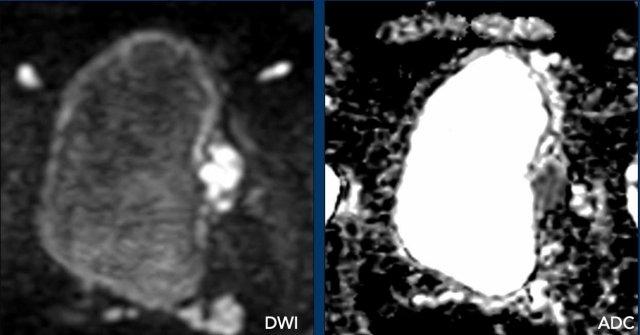

DCE

Có ngấm thuốc sớm của khối u xâm lấn vào mỡ trước bàng quang.

DWI/ADC

Tổn thương xâm lấn mỡ quanh bàng quang tăng tín hiệu trên chuỗi xung DWI, trong khi giảm tín hiệu trên chuỗi xung ADC.

Kết luận

T2W 5, DCE 5, DWI/ADC 5.

Điểm VI-RADS cuối cùng: 5